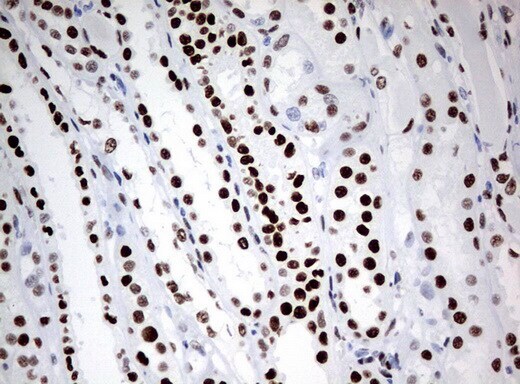

- Immunohistochemical staining of paraffin-embedded human lymph node tissue using anti-ZSCAN18 mouse monoclonal antibody. (UM500081; heat-induced epitope retrieval by 10mM citric buffer, pH6.0, 120°C for 3min)